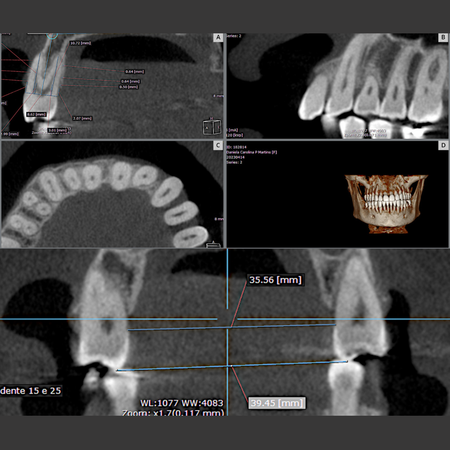

Objetivo: Avaliar as alterações, por meio de Tomografia Computadorizada de Feixe Cônico (TCFC), no osso alveolar vestibular e palatino de pré-molares superiores em indivíduos adultos jovens que foram submetidos à expansão dentoalveolar com alinhadores Invisalign ® e compará-las nos diferentes tipos faciais. Método: Quarenta e cinco pacientes (32 mulheres e 13 homens, média de 34,2 anos) realizaram expansão ortodôntica com alinhadores dentários. TCFCs foram realizadas antes (T0)...

Leia mais

Objective: This study aimed to evaluate changes, using Cone-Beam Computed Tomography (CBCT), in the buccal and palatal alveolar bone of maxillary premolars in young adult individuals who underwent dentoalveolar expansion with Invisalign® aligners, and to compare these changes across different facial types. Methods: Forty-five patients (32 women and 13 men; mean age: 34.2 years) underwent orthodontic expansion with clear aligners. CBCT scans were obtained before (T0) and after expansion of...

Leia maisCopyright © 1996 - 2024 DentalGO | Todos Direitos Reservados. DentalGO é uma marca Dental Press